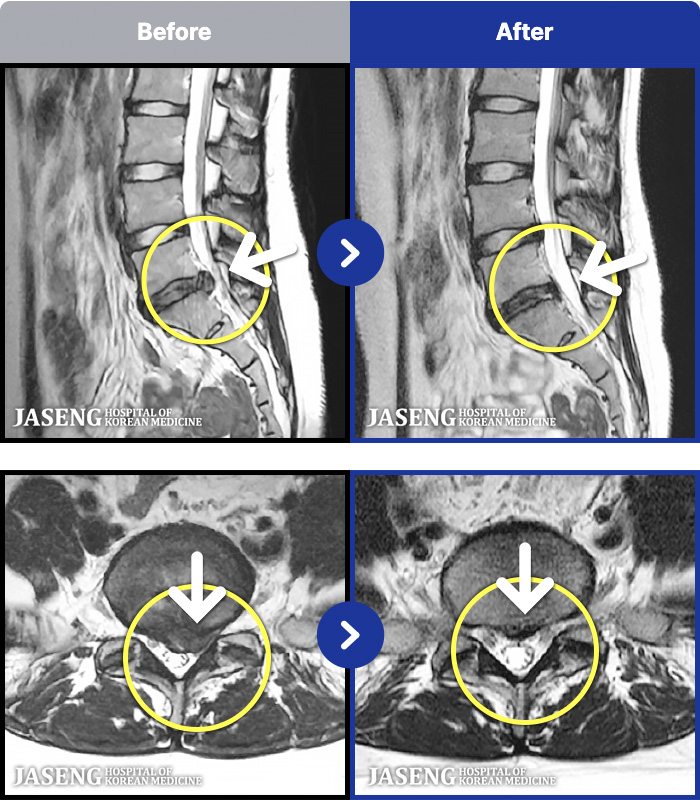

1,293 MRI ũ ʸ Ȯϼ.

Ϻ ߿ Ͽ, ٸ ٱ Ƹ ݵǾϴ. |